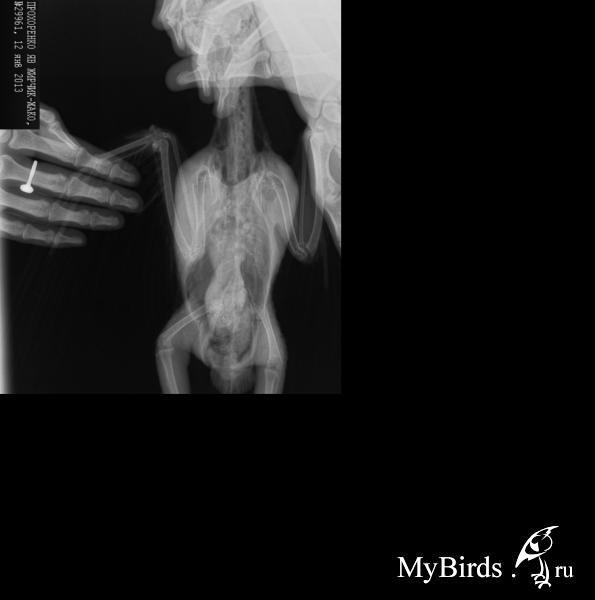

Zosia Опубликовано 23 декабря, 2013 #1 Опубликовано 23 декабря, 2013 Форумчане, вынуждена создать тут тему. Она печальна.Идет ВАЛ аспергиллезников-жакош. Все в тяжелом состоянии.Конечно аспергиллез страшен всем птицам (вот тема Артема,про трагедию с его амазоном Арчи,очень показательная)http://www.mybirds.ru/forums/index.php?sho...hl=%C0%F0%F7%E8Но жаки особые птицы... если тому же амазону можно назначить итраконазол, то жаку- только вориконазол, а он стоит очень и очень недешево.Если еще добавить их "зхрупкость" в части фосфор/кальциевого баланса- то вывод один- для жако аспергиллез в несколько раз более критичен.чем для любого другого сравнимого с ним по гаюаритам птицуна. Поэтому-ДИАГНОСТИКА!Рентген- обязательно. Всем жаковладельцам я бы рекомендовала раз в году делать рентген.При МАЛЕЙШЕМ сомнении- анализы (фарингиальный смыв, помет,биохимия крови). Поймать недомогание на ранней стадии=спасению жизни питомца. 1

Zosia Опубликовано 24 декабря, 2013 Автор #3 Опубликовано 24 декабря, 2013 Я пособираю приличные рентгены и понемножку выложу.Жако сейчас просто сыплются, и почти все с аспергиллой, разной степени запущенности....Ну не подходят наши условия для такой птицы... ни температурные,ни освещение, ни кормовая база.... и ладно коли в Москве/Питере/Киеве/Новосибе... а то в Заполярье, в Байкальске, в Архангельской области... где ни аппаратуры, ни медикаментов.Но есть и какаду, и амазоны, и даже волнистик проскочил. 1

Zosia Опубликовано 31 октября, 2014 Автор #35 Опубликовано 31 октября, 2014 Скажите, какие характерные симптомы при аспергиллёзе? Он внешне хоть как-то проявляется? Отягченное дыхание без признаков выделений из ноздрей, ухудшение летных качеств, у жаконей синеет окологлазной кружок(сердечная недостаточность), светлеет язык, птица упирается головой в стенку или в пол, короткое и неровное дыхание, вдмыается грудь(что птицам несвойственно, у них нет открытго тдыхания диафрагмой), выпячиваются воздушные мешки (ну это уже совсем...). Аспер чаще всего ставят по рентгенснимку,когда обнаруживают гранулемы (аспергилломы).Вот тут они очень характерны

Zosia Опубликовано 28 декабря, 2014 Автор #36 Опубликовано 28 декабря, 2014 Для "освежения" темы, и для того чтобы птицевладельцы понимали.насколько все серьезно- фото с аутопсии полярной совы. Отлично видны аспергилломы и собственно уже спороносящая колония аспергилла.автор фото-Мария Маркина (Полосатая) А это фото уже мое, это колония аспергилл внутри яйца (было с трещинкой видимо) 1